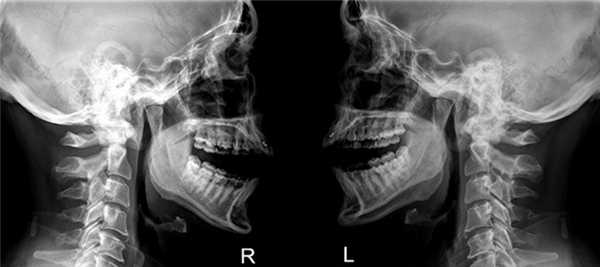

Рентгенография височно-нижнечелюстного сустава

Рентген височно-нижнечелюстного сустава представляет собой один из наиболее распространенных методов диагностики, который позволяет выявить переломы и смещения костей, воспалительные и патологические процессы. Это исследование предельно точно показывает взаиморасположение костных тканей и само строение ВНЧС.

Эта методика используется несколько десятков лет, но ее актуальность сохраняется и по сей день. Основным преимуществом рентгенограммы является передача четкого изображения состояния твердых структур исследуемой области. Работа аппарата основывается на фиксации уровня ослабления радиоактивных лучей, проходящих через твердые и мягкие ткани.

Что показывает снимок ВНЧС?

Снимок ВНЧС – это черно-белое графическое изображение, которое позволяет определить ширину суставной щели, соотношение всей костей, образующих сустав, а также определить имеющиеся патологические процессы.

Для взрослых пациентов лучше всего проводить обзорный метод рентгенографии при помощи дентального аппарата. Чтобы получить наиболее достоверную информацию, исследование проводится с закрытой и открытой челюстью.

Снимок височно-нижнечелюстного сустава показывает следующие результаты: